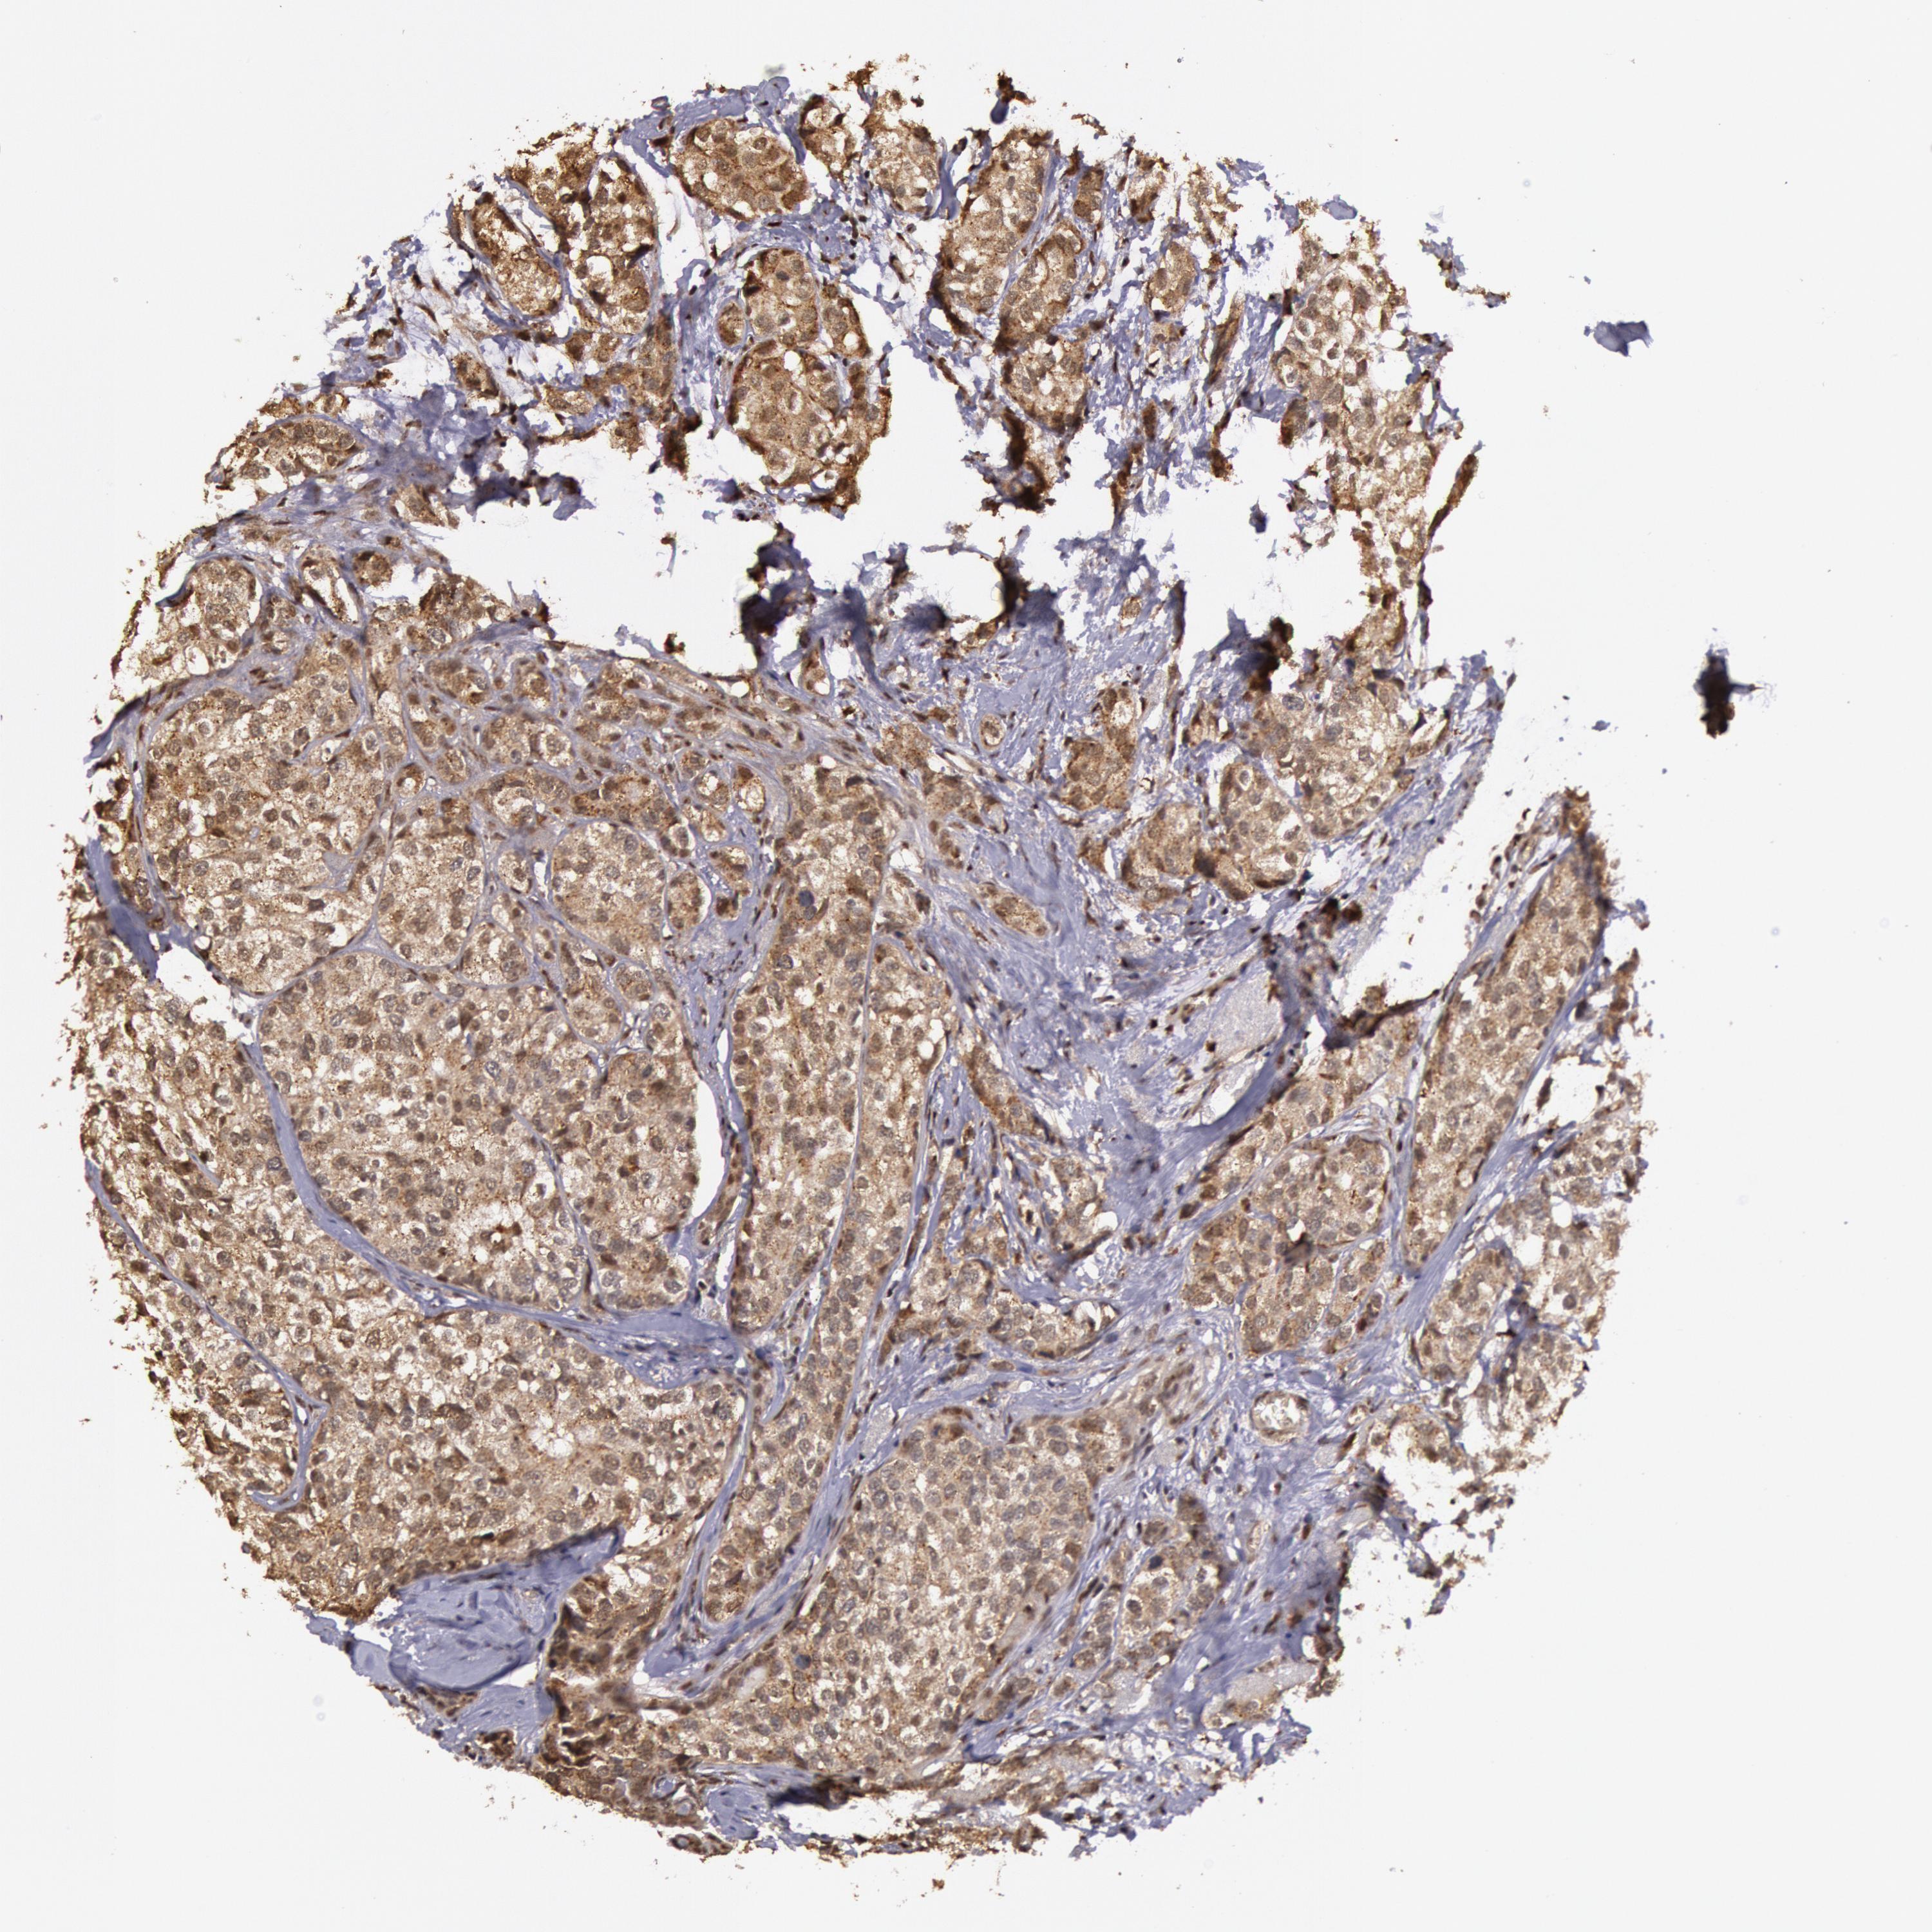

CANCER BREAST CANCER Show tissue menu

BRCA TCGA BRCA VALIDATION PROTEIN EXPRESSION